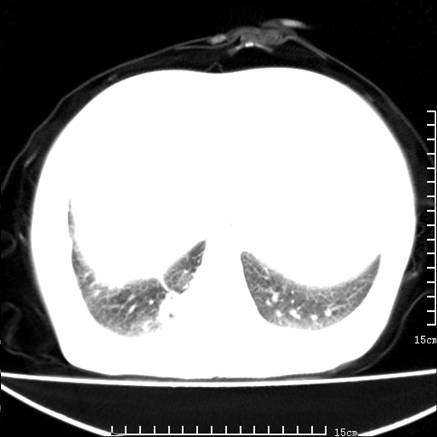

女,王某,58岁,咳嗽三个月余,基层医院二个月前诊为肺结核,用抗结核药二个月无明显疗效。

双肺继发型tb,心功能不全并肺淤血、心包、双侧叶间裂积液,肺大泡,右下胸膜肥厚钙化。

肺窗真难看,建议重做!